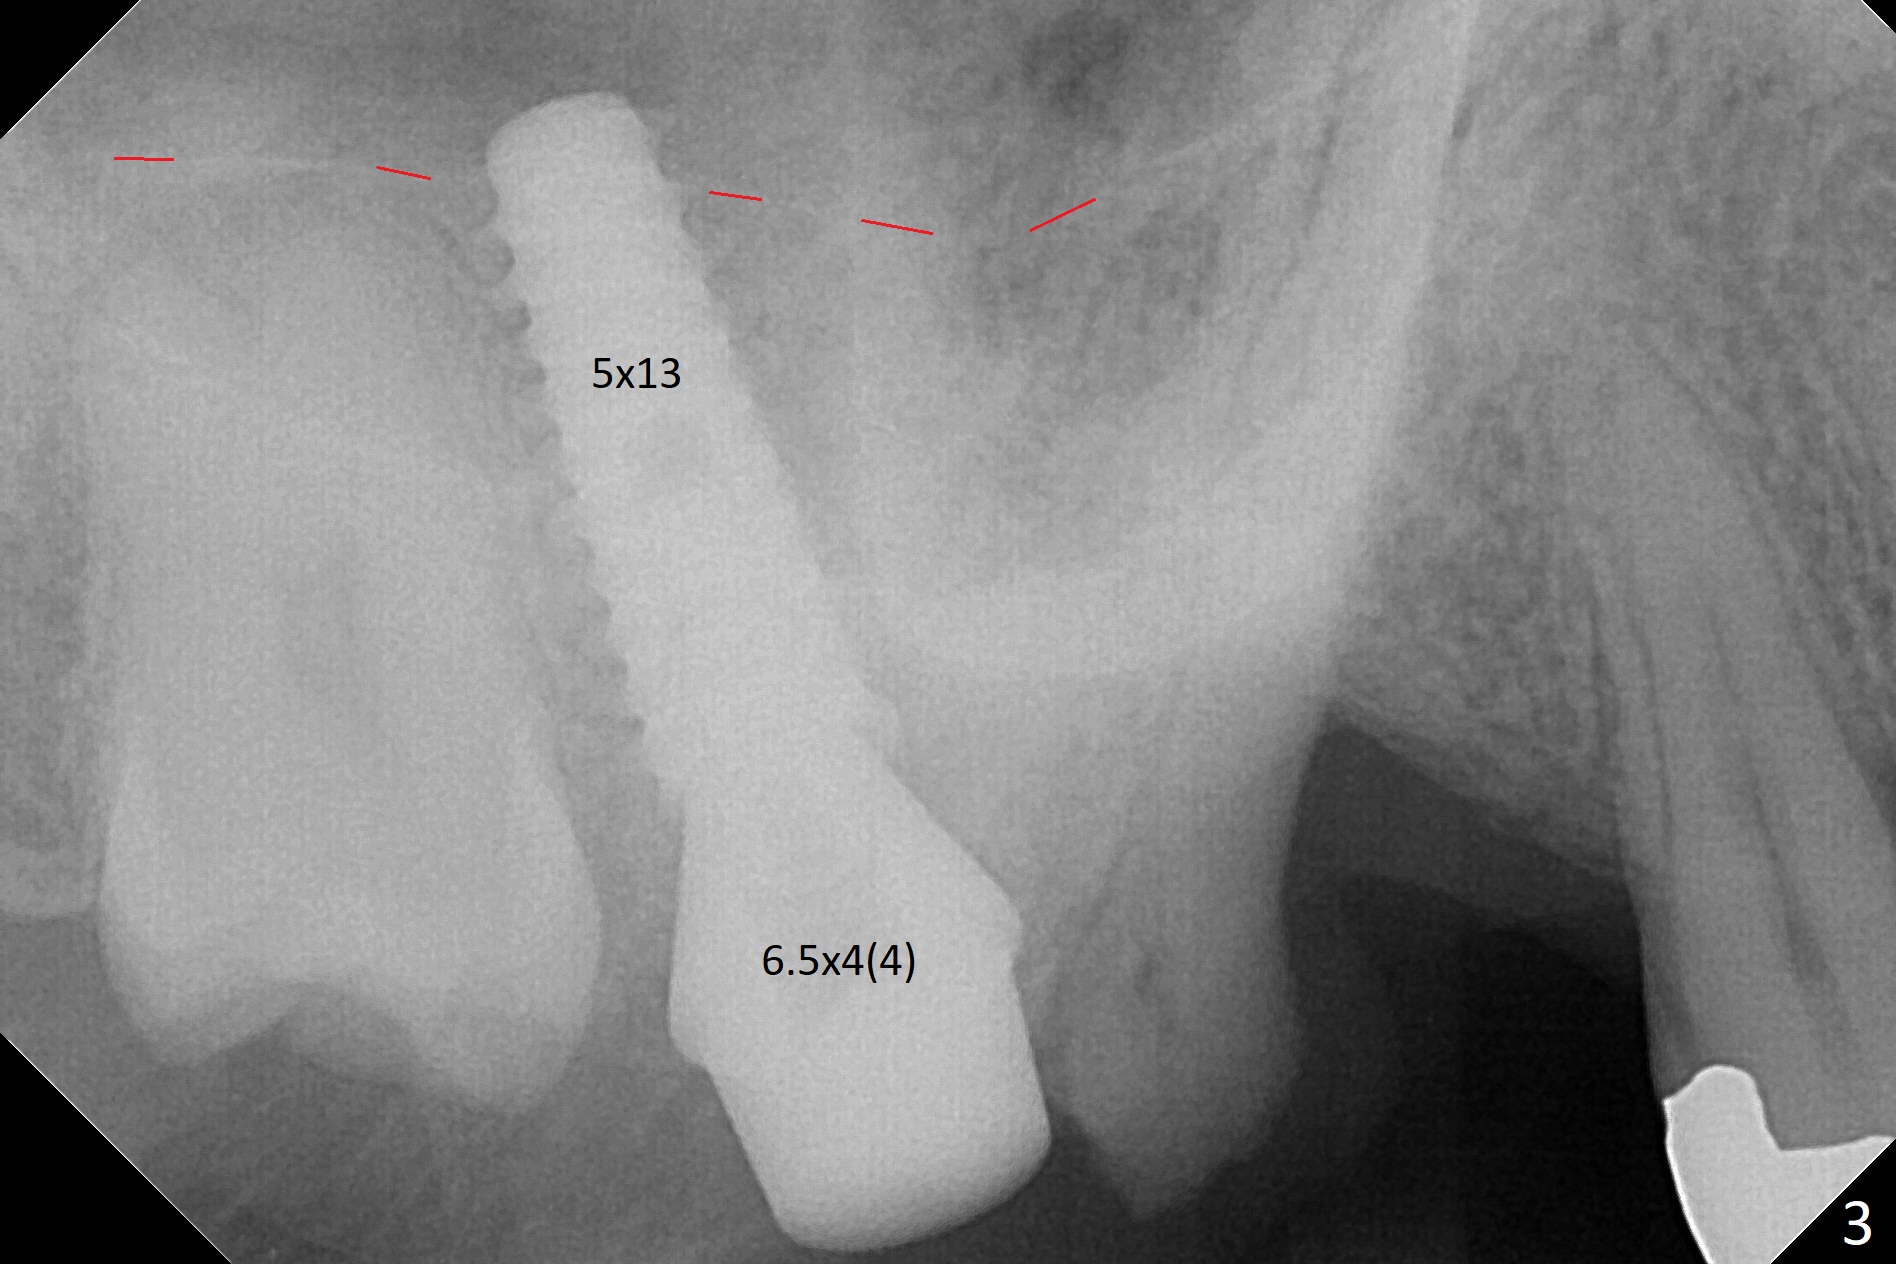

It is difficult to use hard tissue landmark (drill stopper) to make osteotomy in the fresh extraction socket because of socket irregularity and hemorrhage. Once osteotomy is initiated, depth is more reliably controlled with soft tissue landmark (such as gingival margin). This happens in today's case. Without CT information, the osteotomy is established in the buccal slope of the septum of the tooth #2 (after extraction) by using alternatively Magic Sinus Lifter and 4.8 mm Magic Drill (MD). Finally the sinus floor (Fig.1 red dashed line) is lifted after the MD reaches ~16 mm counting from the gingival margin, consistent with preop panoramic X-ray and intraop PA measurement. The 4.5x11 mm dummy implant is close to the impacted 3rd molar (1). Following use of Lindamann bur to move the osteotomy mesially, a 5x9 mm dummy implant is placed away from the 3rd molar (Fig.2 (3: residual root of the 1st molar)). The latter is intentionally not removed in order to maintain osteotomy integrity. A 5x13 mm IBS implant is placed with >50 Ncm; a 6.5x4(4) mm abutment is hand tightened (Fig.3). The remaining large socket is filled with Vera Graft (Fig.4 *). Two months postop, the abutment changes to 6.5x5.7(2) mm without provisional (Fig.5). Nearly 3 months postop, the patient will return for #3 residual root extraction and implant placement with incision (Fig.6). Osteotomy will be initiated in a slope. Prepare surgical round bur for flattening. After placement of a healing abutment, periodontal dressing is to be applied. Take photos to show gingival adaptation to the new abutment without implant exposure at #2.